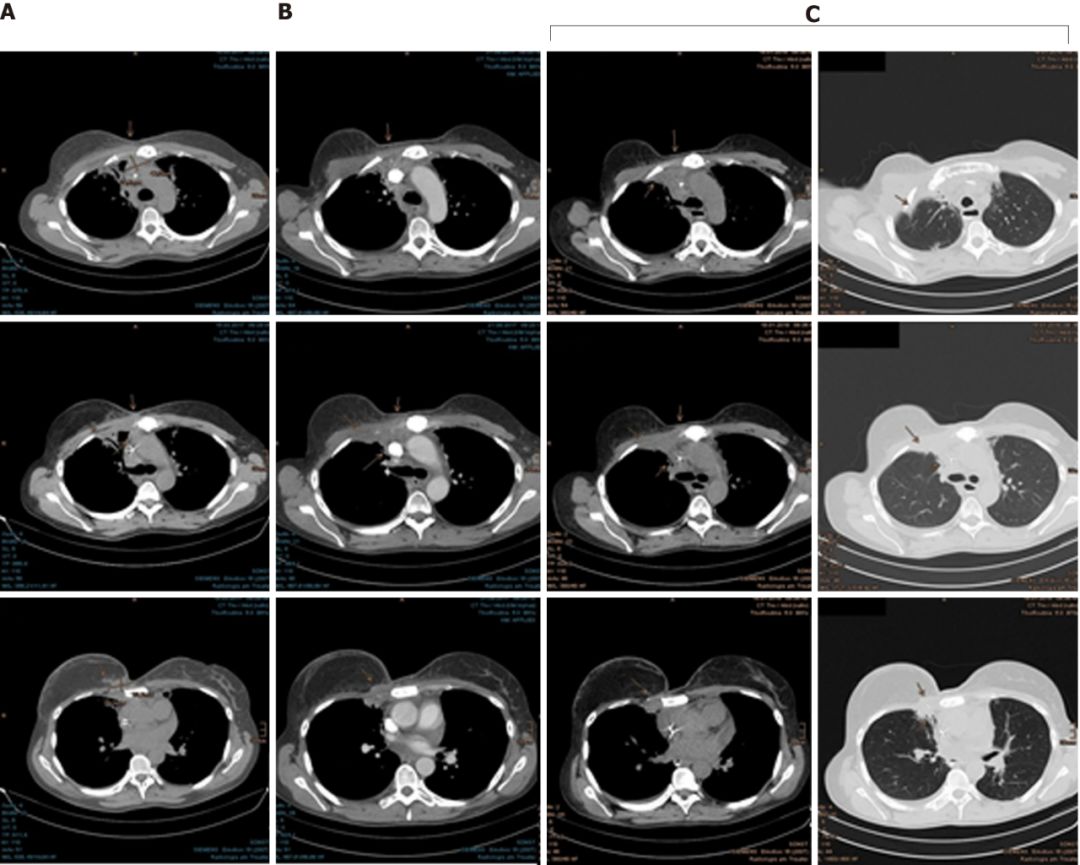

2016年11月至12月,Mary接受了右侧胸骨肿瘤以及邻近胸膜,右侧腋窝,胸骨旁和纵隔区域的淋巴结转移的质子放疗。

幸运的是,Mary对质子治疗的耐受性很好,仅出现了轻微的咳嗽和反流。由于对肺部有一定的辐射剂量,她吃了一些环丙沙星预防放射性肺炎的发生。随后的检查结果显示,癌细胞终于耐不住质子的强烈攻击,开始节节败退,病灶在一次次的缩小。

在最近一次CT扫描中,仍然没有发现肿瘤进展迹象。为了预防病情进展,Mary现在继续使用来曲唑和denosumab进行全身治疗。